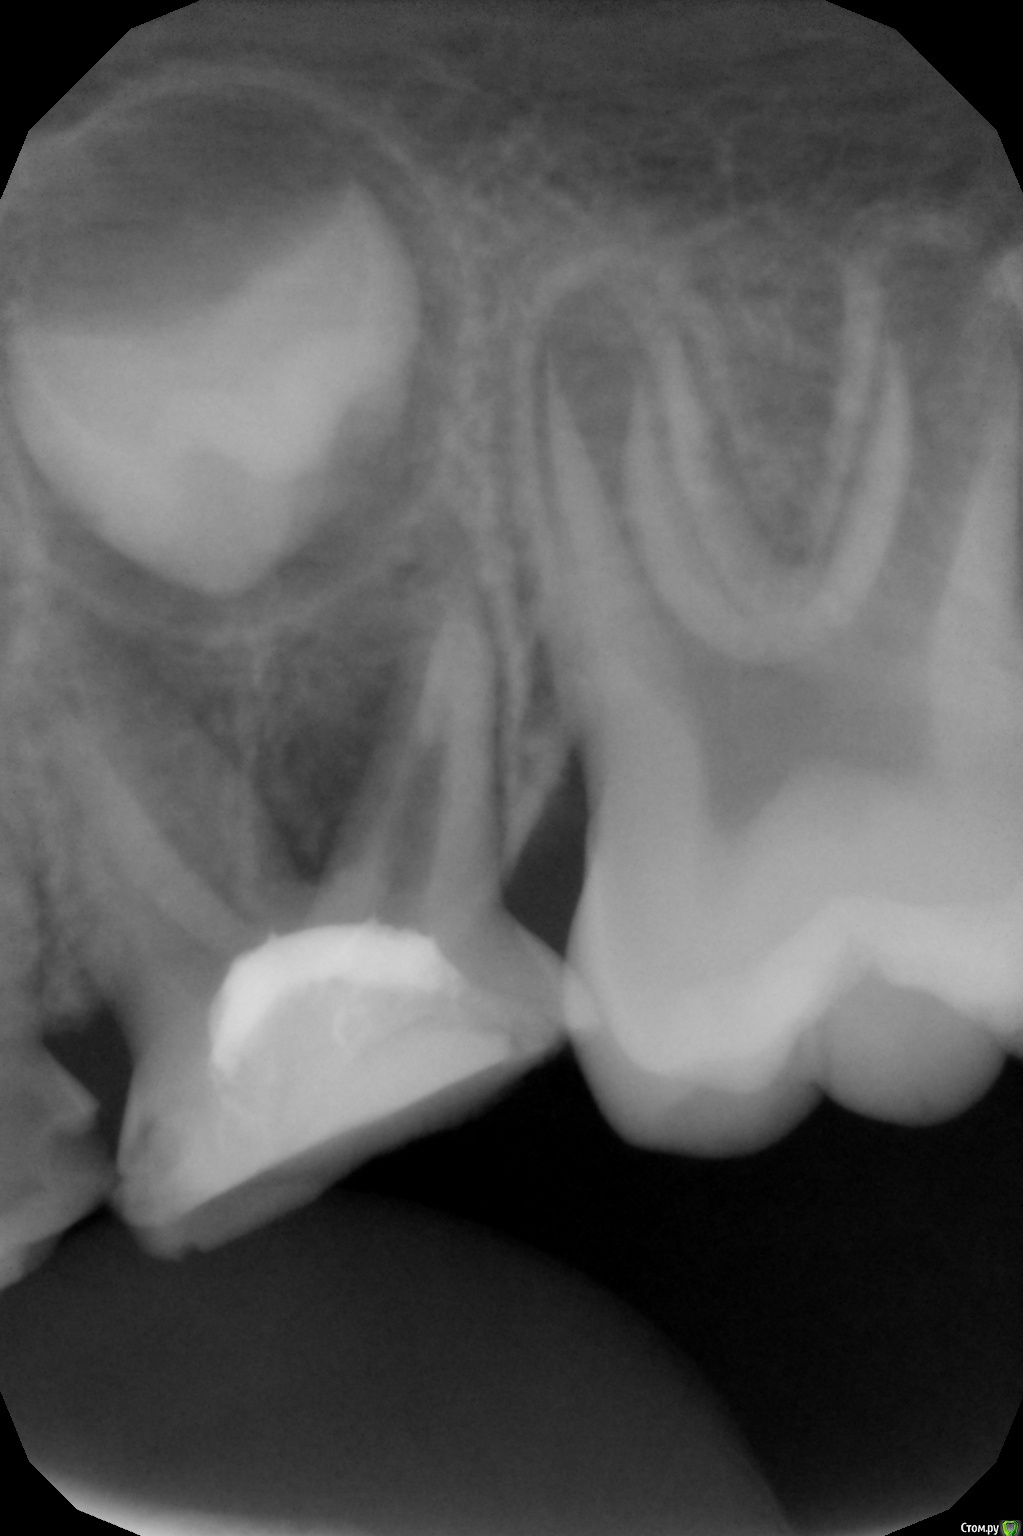

crown Опубликовано 13 июня, 2016 Поделиться Опубликовано 13 июня, 2016 5,5 лет, 8.5 - ранее лечен рф методом. Смущает дистальный корень, боюсь в процессе эндо будет перфо. Что думаете? Ссылка на комментарий

Джима Опубликовано 14 июня, 2016 Поделиться Опубликовано 14 июня, 2016 может, уже есть. машиной не лезьте, только руками, и родителям сразу говорите, что это "разведка боем", диагностическое препарирование, которое может закончиться удалением. временную с кальсептом, под ней видно будет, "пойдёт" зуб, или лучше удалить. 1 Ссылка на комментарий

crown Опубликовано 14 июня, 2016 Поделиться Опубликовано 14 июня, 2016 может, уже есть. машиной не лезьте, только руками, и родителям сразу говорите, что это "разведка боем", диагностическое препарирование, которое может закончиться удалением. временную с кальсептом, под ней видно будет, "пойдёт" зуб, или лучше удалить.Я так понял если будет кровить после кальсепта то удаление. Что то зачастили периодонтиты вот еще один. Что с этим делать? Ссылка на комментарий